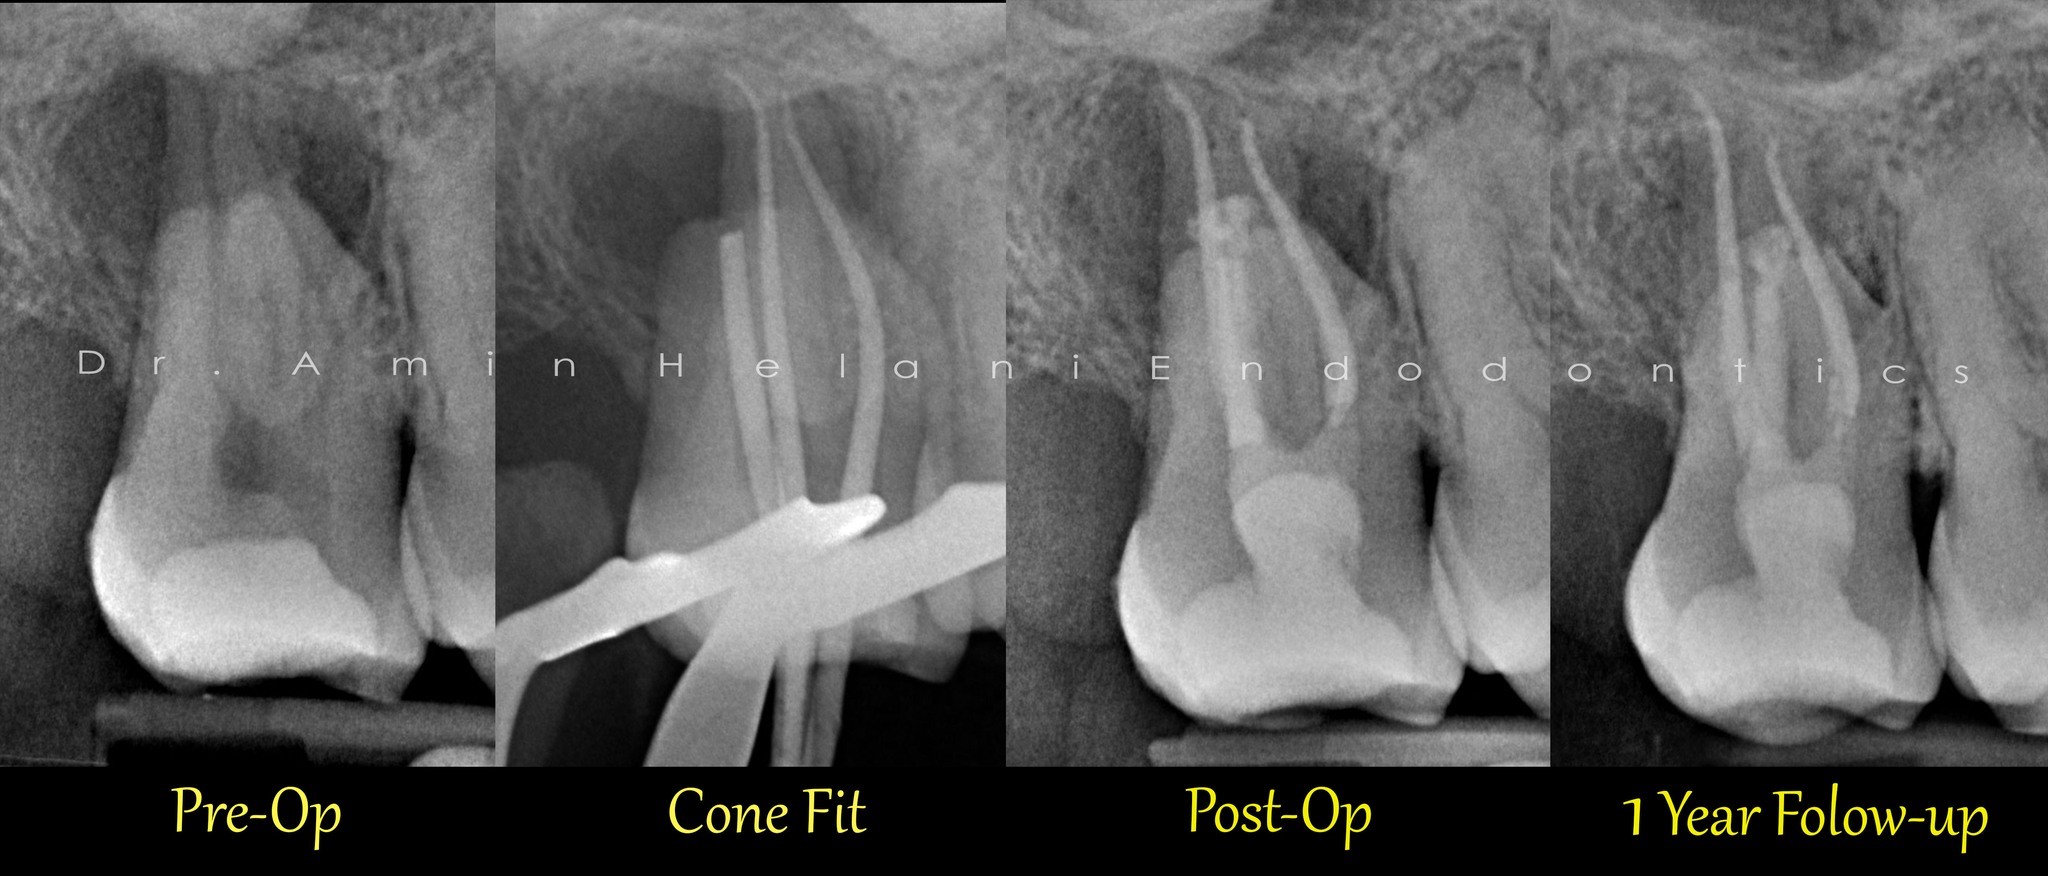

Heilung eines großen interradikulären Entzündungsherdes